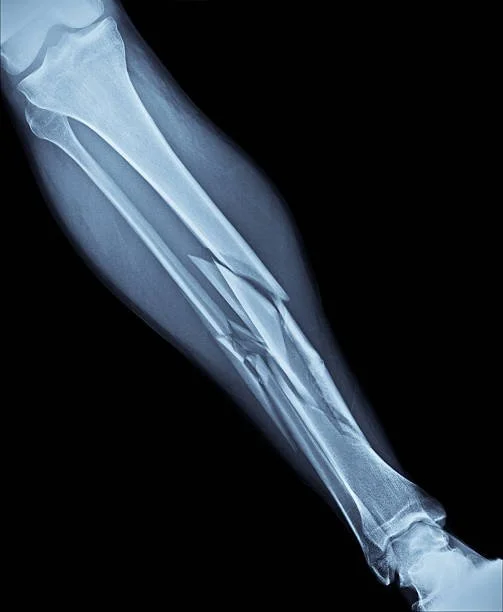

Recovering from an injury often tends to be more straightforward: Break a bone, see it on an x-ray, get fitted for a cast, and the bone should heal properly. Get an infection, take some medicine, the symptoms should go away in a few days.

So no, this is not a perfect analogy. But I imagine it’s probably easier for many of us to understand, simply because we can often see many of these things with our own eyes and touch them with our own hands. We can see an x-ray or ultrasound, or a temperature reading on a thermometer. We can feel ourselves sweat or get the chills, our stomachs turning from not eating enough or from overindulging.

When we know something is going on with us physically, in many cases, there is a perception, an expectation, a stigma that there is such a thing as getting “back to 100 percent”. We hope that one day, we’ll be free of our illness, that we’ll no longer be sick, that we’ll have fully recovered. “Cured,” if you will.

I believe that there is a stigma that when we seek help for our mental health, we should expect to “get better” the same way we get over a cold or heal from a broken bone. A stigma that says you shouldn't have to keep getting help indefinitely. A stigma that says that one day, you should eventually be "cured…"